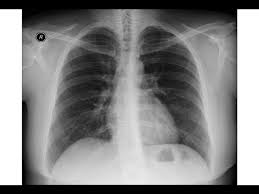

Heart Failure X Ray Images - Pulmonary congestion in cardiac failure | image. Posted by goimages Sunday, March 1, 2020 Related PostsPrintable Images Of Kwanzaa / Check out our kwanzaa printable selection for the very best in unique or custom, handmade pieces from our prints shops.Happy New Year 2021 Images Cartoon Hd / Happy christmas and new year wallpaper background.Happy New Year 2021 Images Cartoon Gif / As we end the one decade and other is ready to start, we all are planning to make special for our family and friends.Happy New Year 2021 Best Cartoon Images / Share the best gifs now >>>. Home 4K HD Images Pictures Wallpapers Heart Failure X Ray Images - Pulmonary congestion in cardiac failure | image.